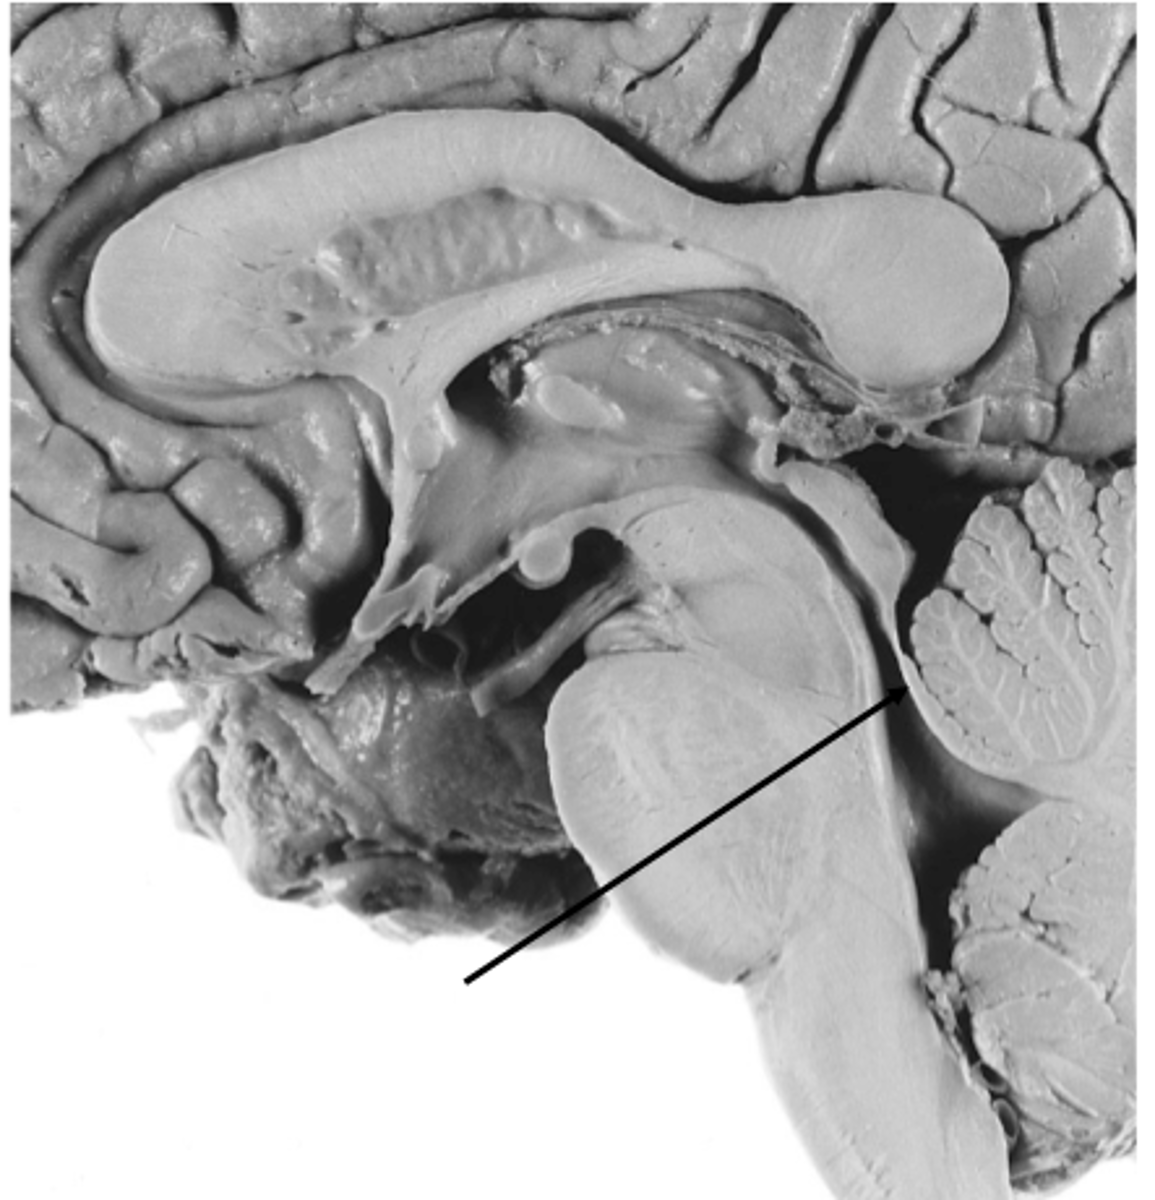

refers to the rostral portion of the medulla since there is no medullary tissue here on the dorsal aspect of the 4th ventricle

open

refers to the caudal portion of the medulla since there is medullary tissue here on the dorsal aspect of the 4th ventricle (therefore it is enveloped by the medulla)

closed

narrowed down portion of the 4th ventricle in the closed portion of the medulla

central canal

two ridges of tissue on the ventral aspect of the medulla, separated from each other by the ventral median fissure

pyramids

area where most corticospinal fibers decussate over the lower medulla, therefore obscuring the ventral median fissure

pyramidal decussation

elongated mounds of tissue lateral to the medullary pyramids

olives

vertical groove dorsolateral to the inferior olive on each side that gives rise to CN IX and X

postolivary sulcus

white matter stalks that connect the medulla to the cerebellum

**these help to form the lateral walls of the caudal portion of the 4th ventricle

inferior cerebellar peduncles

medial paired ridges of tissue on the dorsal aspect of the closed portion of the medulla

tractus gracilis

lateral paired ridges of tissue on the dorsal aspect of the closed portion of the medulla

tractus cuneatus

superior ends of the medial paired ridges of tissue on the dorsal aspect of the closed portion of the medulla, formed by namesake nuclei

gracilis tubercles

superior ends of the lateral paired ridges of tissue on the dorsal aspect of the closed portion of the medulla, formed by namesake nuclei

cuneatus tubercles

V-shaped boundary of the caudal aspect of the 4th ventricle that marks the boundary between the open and closed portions of the medulla

obex

name the groove

pontomedullary junction

general portion of the medulla

open medulla

general portion of the medulla

closed medulla

pyramids

ventral median fissure

pyramidal decussation

C

inferior cerebellar peduncles

cuneate tubercle

gracilis tubercle

cuneatus tract

gracilis tract

obex